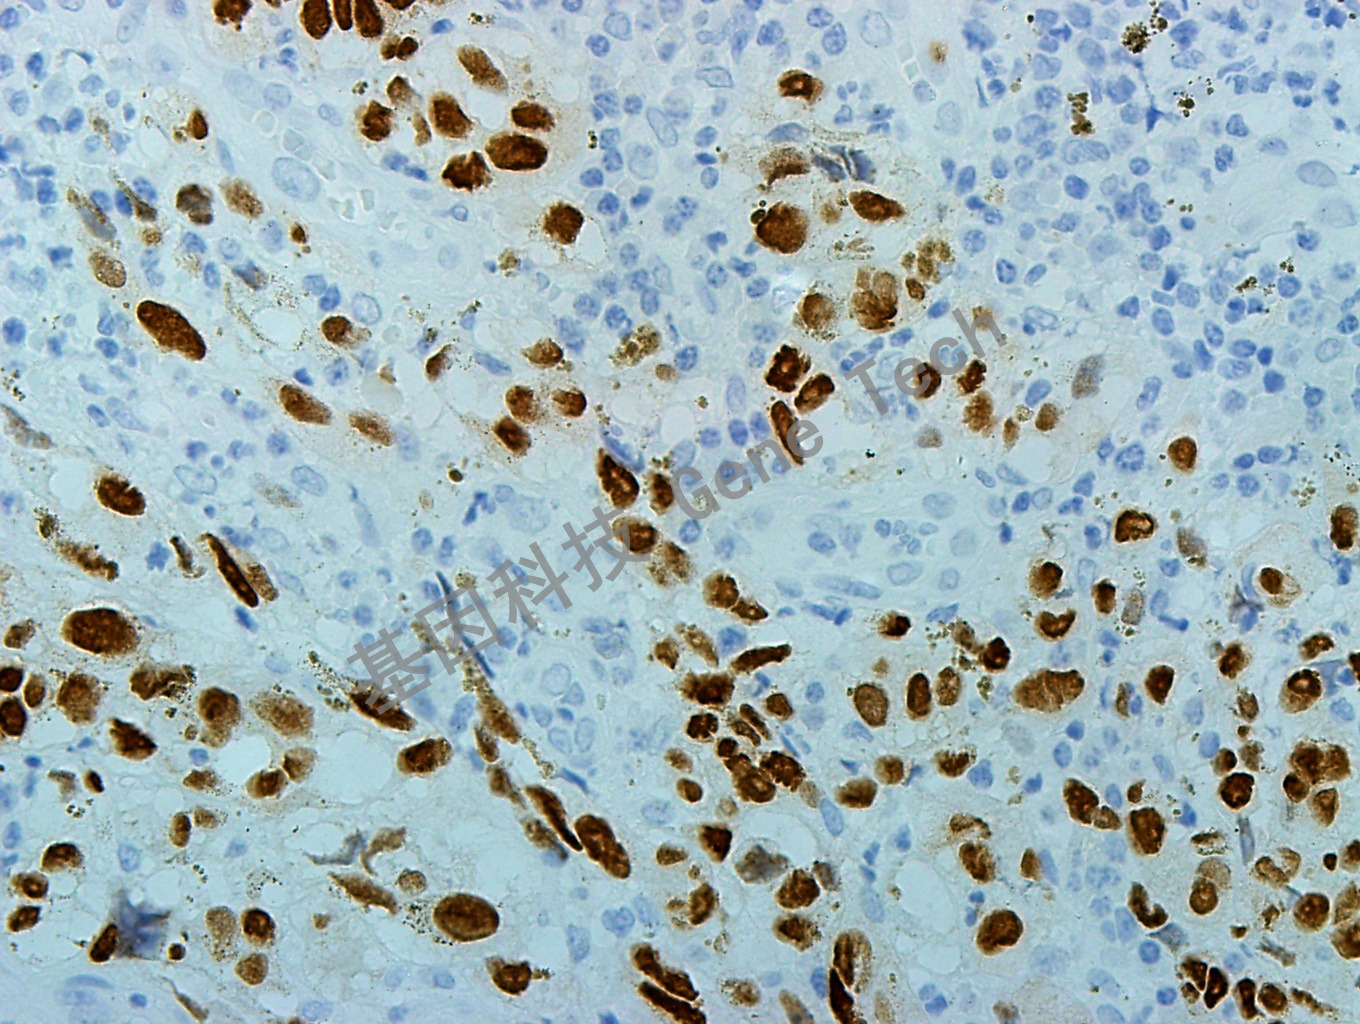

| 預(yù)處理:高pH熱修復(fù) | 陽性部位:細(xì)胞核 | 陽性對照:黑色素瘤/雪旺氏細(xì)胞瘤 |

| 黑色素瘤石蠟切片,用 SOX-10(GT2210)染色,細(xì)胞核陽性,DAB 顯色。 | ||